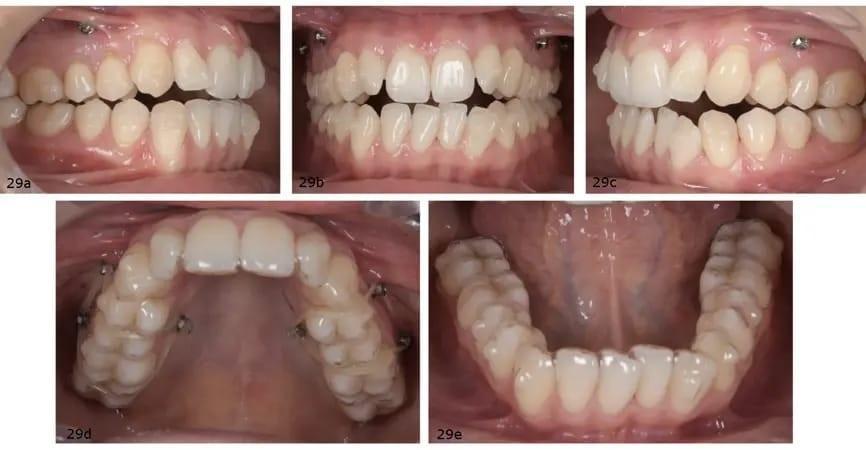

Поскольку для обеспечения авторотации нижней челюсти требуемая интрузия задних зубов верхней челюсти превышала 1 мм, были рекомендованы межрадиулярные мини-винты для увеличения приложения усилия и обеспечения контролируемого вертикального перемещения (фото 28). На первом приеме были прикреплены аттачменты в соответствии с цифровой настройкой. В верхнюю челюсть было вживлено в общей сложности шесть мини-винтов: четыре с буккальной стороны между первым и вторым премолярами и два с небной стороны между первым и вторым молярами. Пациентке было рекомендовано надеть эластики с двух сторон поверх элайнеров и закрепить их мини-винтами для облегчения задней интрузии (фото 29).

Фото 29a–e Ситуация после установки верхнечелюстных и нижнечелюстных аттачментов и мини-винтов (a–c). Эластики на верхнечелюстном элайнере (d). Нижнечелюстной элайнер после установки аттачментов (e).